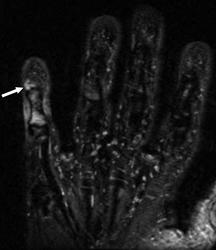

Хондрома периостальная.

Периостальная хондрома (син.: юкстакортикальная хондрома, паростальная хондрома редкая доброкачественная опухоль, состоящая из зрелой хрящевой ткани и расположенная над надкостницей. Обычно она разрушает наружную часть коркового слоя, но не прорастает в костно-мозговой канал. Мужчины болеют в два раза чаще женщин. Типичная локализация - проксимальный конец плечевой и бедренной кости дистальный конец бедренной кости, а также фаланги. В редких случаях одновременно поражается несколько костей. Периостальная хондрома обнаруживается большей частью в метафизарной части, лишь у 30 % больных поражаются диафизы. Опухоль достигает в среднем 2-3 см в диаметре. Она окружена зоной остеосклероза и сопровождается периостальным остеогенезом, так что на границе опухоли с костью образуется грушевидное углубление с четкими контурами. Под микроскопом периостальная хондрома имеет тонкие контуры, она как бы погружена в корковый слой и покрыта надкостницей, как тонкой скорлупой. На разрезе ее ткань синюшно-серая или белая, хрящевые элементы обладают дольчатым строением. Участки обызвествления имеют вид желтовато-белых вкраплений. Эта опухоль состоит из гиалинового хряща, дольки которого разделены фиброзными прослойками или костными балками, местами обызвествленными. Кое-где отмечается проникновение опухолевых клеток в костномозговой канал, на большем же протяжении внутренний контур образован компактной костью.